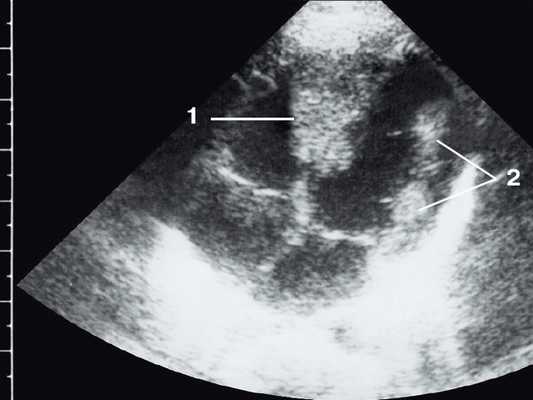

Широкое внедрение в практику ультразвуковой диагностики позволило перейти от аутопсийной статистики к прижизненному выявлению. Эхокардиография – первый метод выявления рабдомиомы сердца и контроля состояния пациента в динамике. Учитывая очень большое число семейных случаев, необходимо обследование всех ближайших родственников, особенно при наличии у них пятен цвета кофе с молоком, депигментированных по типу шагреневой кожи, параунгвальных и параореолярных фибром, ранних миом матки, инфантильных спазмов, судорожных припадков и других признаков факоматозов. При семейных обследованиях рабдомиомы сердца могут выявляться у совершенно бессимптомных носителей (рис. 1, 2).

Рис. 1. Эхокардиограмма ребенка (девочки) с рабдомиомой. Крупный узел рабдомиомы в межжелудочковой перегородке (1) и менее крупные узлы в задней стенке левого желудочка (2). Эхоплотность образований выше, чем миокарда.

Рис. 2. Эхокардиограмма матери этого же ребенка. В межжелудочковой перегородке несколько эхоплотных образований (стрелки).

Рабдомиома сердца эхографически выглядят как достаточно четко очерченные образования. Чаще всего располагаются в миокарде левого желудочка, реже – в правом, еще реже – в предсердиях, кавоатриальных и атриовентрикулярных соединениях, эпикарде. Метастазирование не типично [8]. Наличие двух и более рабдомиом четко коррелирует с туберозным склерозом, одиночные рабдомиомы сердца такой связи, как правило, не имеют. По нашему опыту (18 пациентов), чем меньше объем новообразования, тем выше акустическая плотность, приближающаяся к эталонной эхоплотности (эндо-, эпи- и перикард). Эхоплотность больших рабдомиом практически не отличается от эхоплотности миокарда. В толще новообразования выявляются мелкие эхонегативные очажки (области некрозов) и эхопозитивные очажки (отложения кальция) (рис. 3).